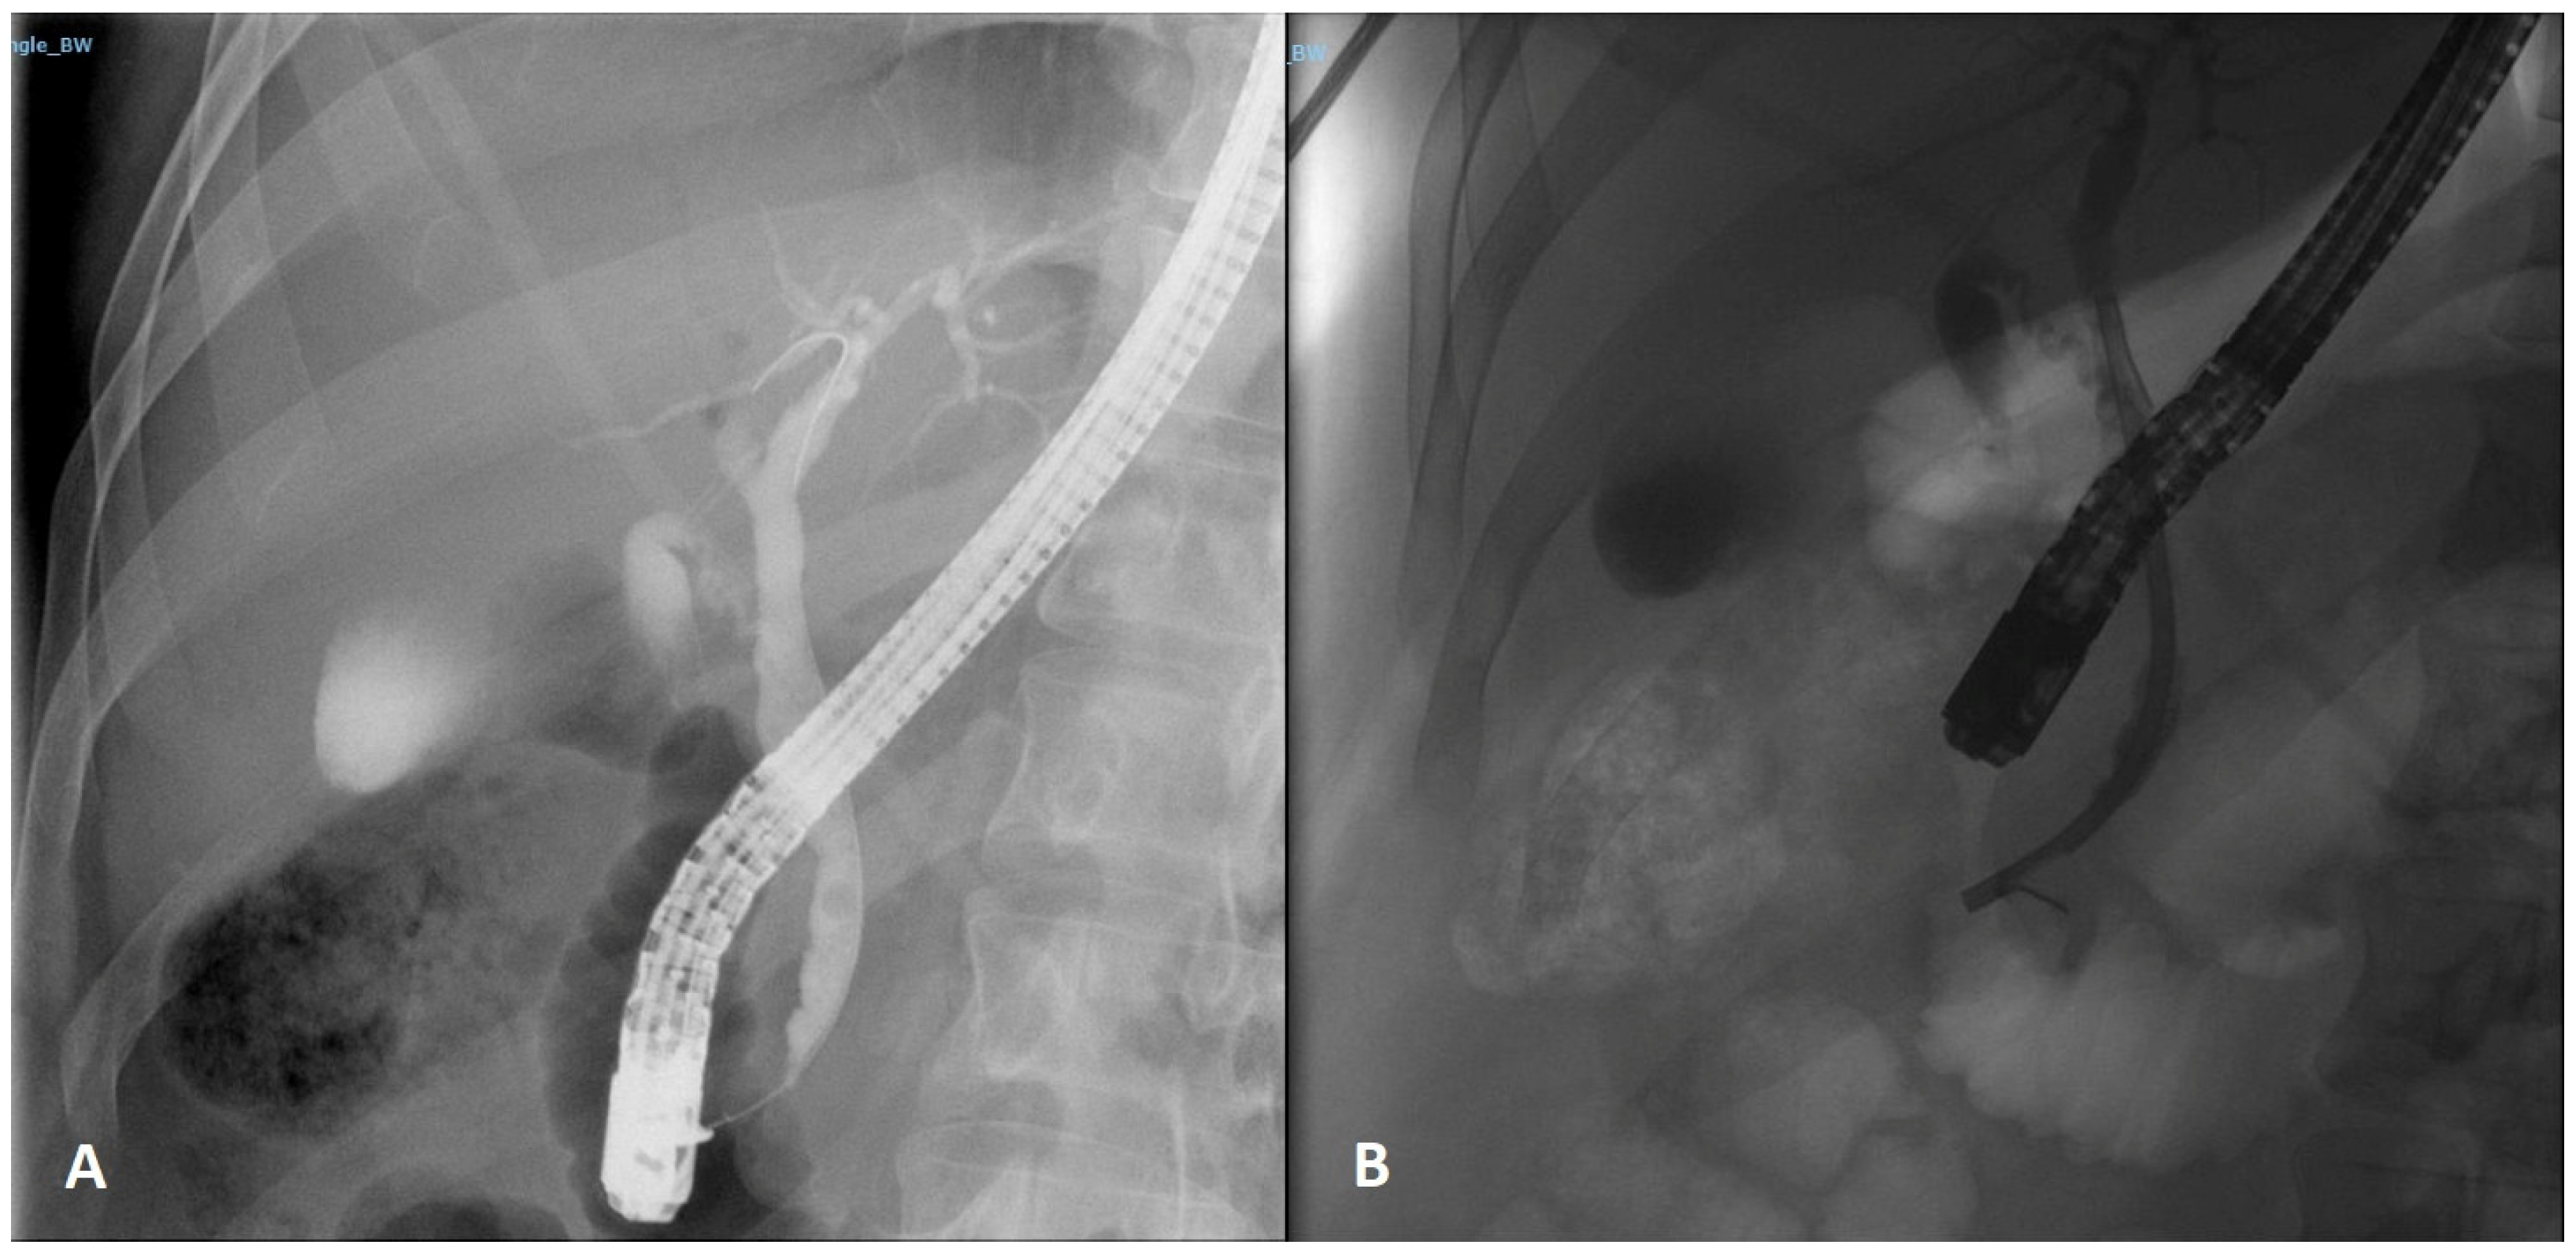

2. Case Report 1

3. Case Report 2

4. Case Report 3